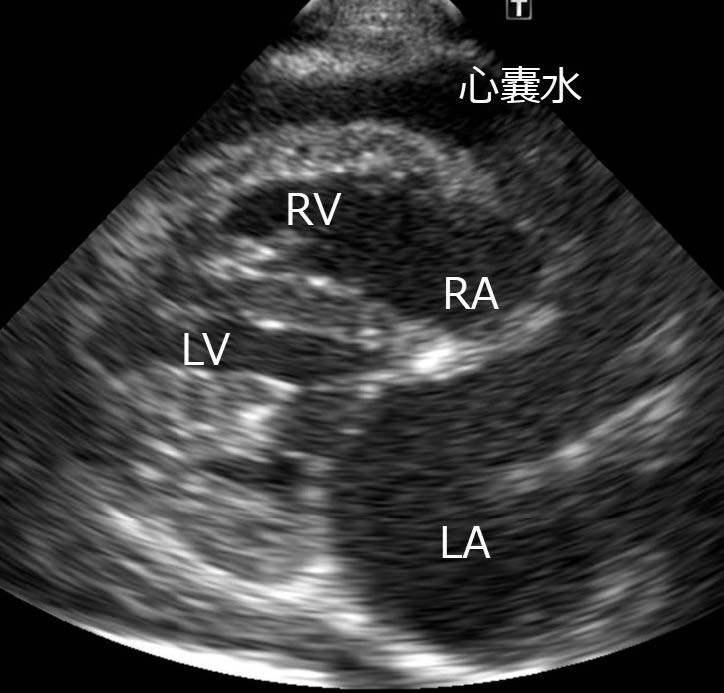

ポイント・オブ・ケア胸部超音波検査:図1 及び2

図2 右傍胸骨長軸四腔断面

図1 は症例の左側胸壁からの肺エコー像で,正常な肺で観察されるA ラインを示している.正常であれば高エコー性に描出される肺胸膜ラインの下方に多重反射により形成されたA ラインが認められる.肺水腫であった場合には肺胸膜ラインから垂直方向に減衰せずにA ラインをかき消す高輝度線状アーチファクトであるB ラインが観察されることがある.本症例では両側いずれの領域においてもBラインが認められなかったことや経皮的動脈酸素飽和度が正常であったことから,急性心不全による肺水腫は否定的と判断した.図2 は心膜液貯留と心膜腔内の血餅を疑う構造物を示している.心外膜の外側(心膜腔)に無エコー性の液体貯留が認められることから心膜液貯留と判断できる.さらに一部に血餅を疑うエコー源性のある構造物が存在することから左心房破裂による心膜液貯留と診断することができる.本症例はこれまで心不全に起因していると考えられる症状(頻呼吸,呼吸困難など)を呈しておらず,胸部X 線検査と心臓超音波検査で心拡大の基準(EPIC 基準)を満たしていたことからMMVDACVIM stage B2 と診断された.左心房破裂は心不全を呈したことのないstage B2 でも認められることがある(15 頭中6 頭がstage B2)と報告されているため,心不全の既往がなかったとしても除外できない点に注意する必要がある[1].

心タンポナーデの有無は,心膜液の貯留量では評価できず,収縮期(心房が拡張している時相)において右心房が虚脱(内側にへこむ)しているか否かで判断する(図3).直後の評価では心タンポナーデではないと判断した場合でも,貯留量が増加してくることで変化する可能性もあるため,経時的な観察が推奨される.

図3 収縮期における右傍胸骨長軸四腔断面右心房は虚脱していなかったことから心タンポナーデは呈していないと判断された.